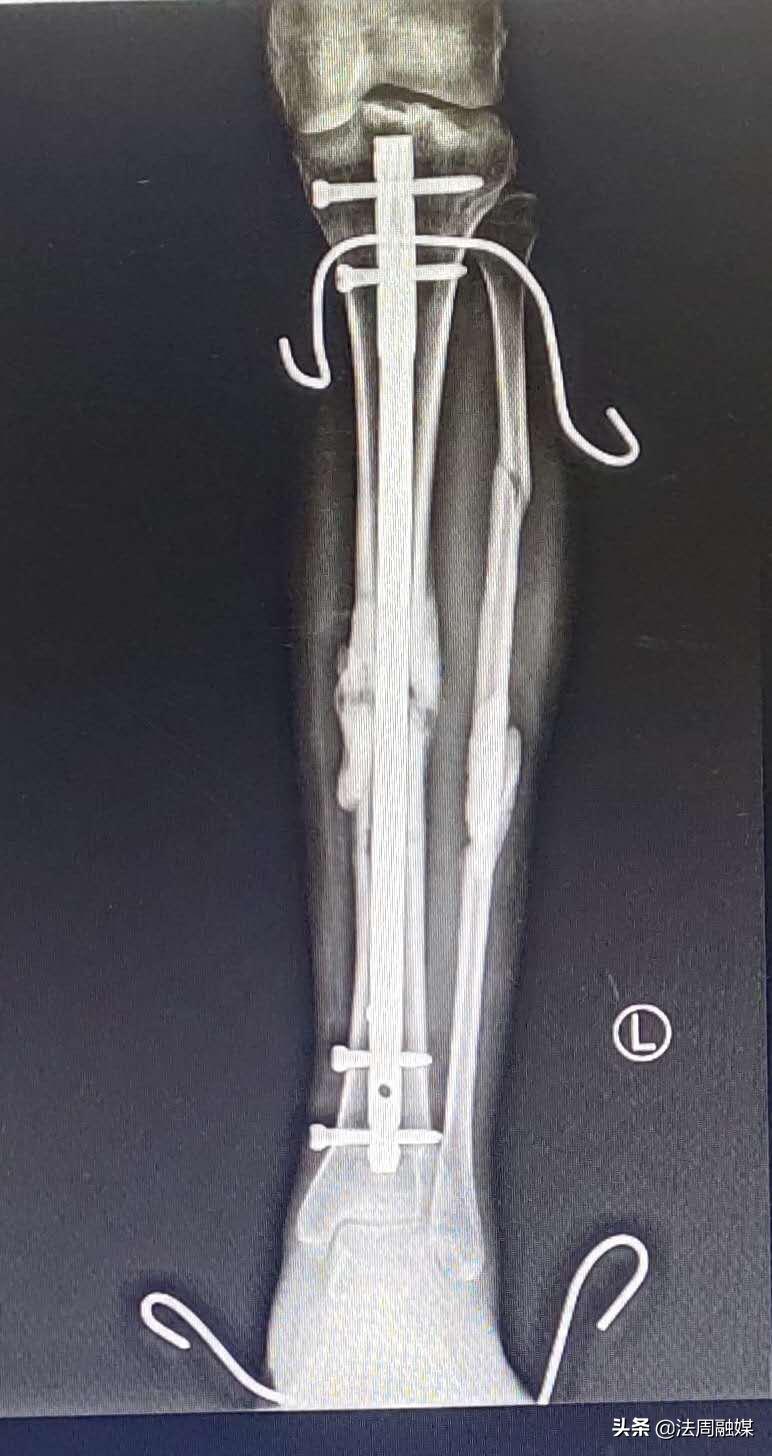

由于损伤严重,骨缺损,小文在后期康复中,骨折部位愈合不良并出现“马蹄内翻足”,站立行走困难。此时,肖群飞想出了奇招,去除外固定架,闭合扩髓达到植骨目的并髓内钉固定促进骨折愈合,再利用“克氏针配合橡皮筋”持续牵引纠正马蹄足内翻。后来,经过医生的精准治疗和自身不断的康复锻炼,小文逐渐站立起来,筑立起了明日美好的生活!

“克氏针配合橡皮筋”持续牵引纠正马蹄内翻足,可避免繁杂的畸形松解手术,使患者以最小代价得到最好的康复。

外固定支架+抗生素骨水泥+VSD治疗严重胫腓骨开放性骨折,相对于传统的内外固定技术有着较大的优势,外固定支架治疗原则“简单、迅速,有效”,固定可靠,软组织干预少,安装快捷,有利于损伤控制。外固定支架良好的架空技术可以在不影响骨折端的情况下同时对软组织创面进行观察、换药、植皮等手术处理。VSD(负压封闭引流技术)引流通畅,可以保证创面清洁,阻止感染的扩散,且改善局部微循环,促进创面愈合,减少天天换药给患者带来的痛苦,能让患者降低医疗费用。抗生素骨水泥能有效预防及治疗感染,对于骨折后期愈合不良者,闭合扩髓交锁钉内固定,既能免除取髂骨带来的新的痛苦,又促进了骨折愈合及康复。(来源:常德市第一中医医院)